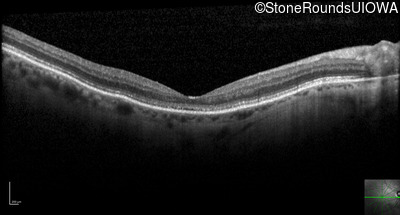

Optical Coherence Tomography - Right - 20/250

Exemplar / OCT Stack